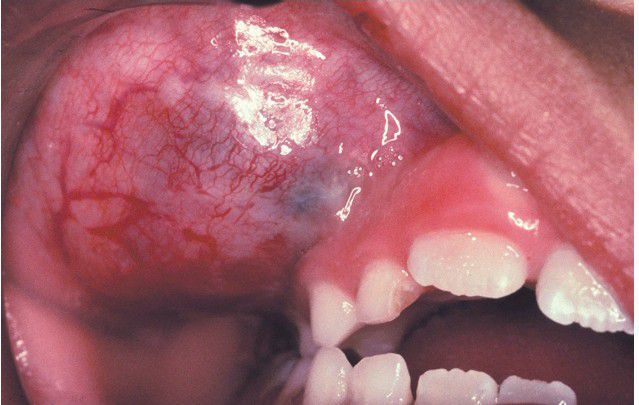

Embryonal Rhabdomyosarcoma

Young child with a mass of the right maxilla.

Maxilla

Mass

Rhabdomyosarcoma